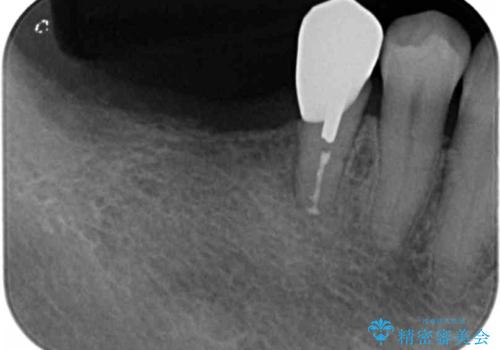

骨は薄くなってしまい、インプラントの長期的な安定を見込むには不十分でしたのでインプラントの埋入と同時に周囲にコツの造成を行う治療計画を立てます。

- 81.4万円 (straumann社製インプラント×2 アバットメント×2 仮歯×2 骨造成 ジルコニアクラウン×2)費用は治療当時の料金となります